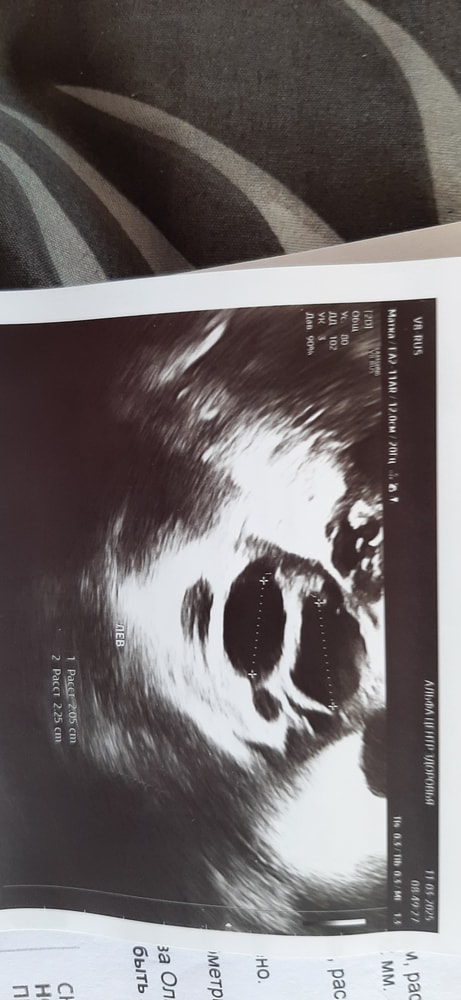

Маруся Марусина, вот еще пару снимков Изображение Изображение

Маруся Марусина, заключение Изображение

Татьяна, по заключению доминантного фолликула нет. А вот, что за образование не понятно вообще, в заключении размеры одни, на снимке другие... странный узист. Переделайте узи в другом месте!!! Это не компетентный специалист!